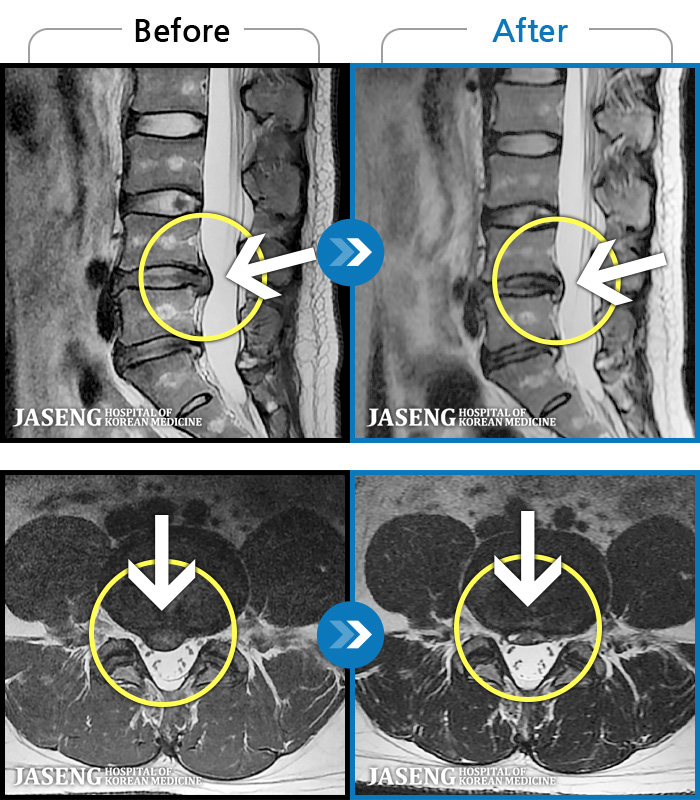

1,241 MRI ũ ʸ Ȯϼ.

㸮, ٸ ٷ

ǿ

ȯ

㸮ũ

¥

2019.11.29

[] 18.04.09~18.12.05

ȯںп Ǹ ǿ ԿǾ, ο ġ ۿ Ƿ ġḦ Ͻñ ٶϴ.